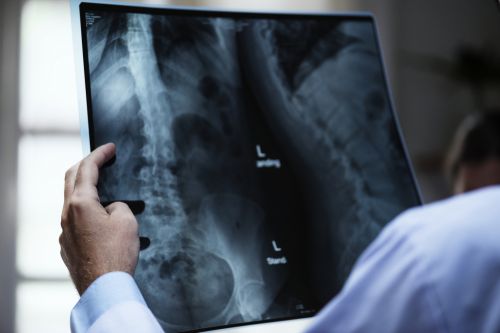

Хирурги будут делать любую операцию, соответствующую точной проблеме с позвоночником. Это будет запланировано против общих клинических признаков и результатов сканирования, таких как рентгеновские снимки.

Примеры хирургических процедур лечения осложненного спондилеза включают:

- Удаление диска или кусочка кости, вызывающего проблему с нервами - соседние позвонки сливаются после операции;

- Замена диска - искусственный диск заменяет изношенный.